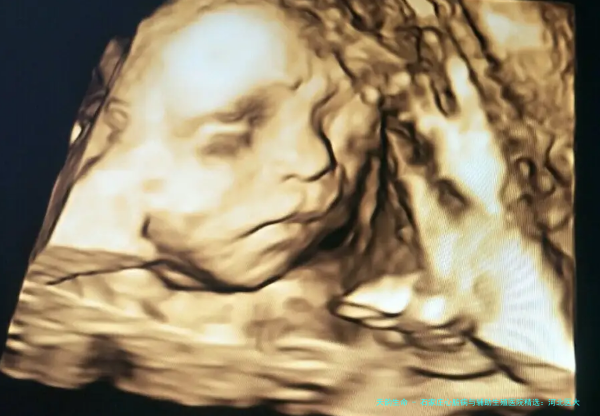

对于得了心脏病的生育年龄人群,自然怀孕和制造过程可能给心脏带来巨大承当,存在较高危。在专业心血管医生评估和监护下,通过人类辅助生殖技术(如试管婴儿)科学方案妊娠,成为一种更安全的选择。这要求医院不仅生殖中心技术过硬,其心里科、产科、麻痹科等多学科协作(MDT)能力也必须颇为强大。